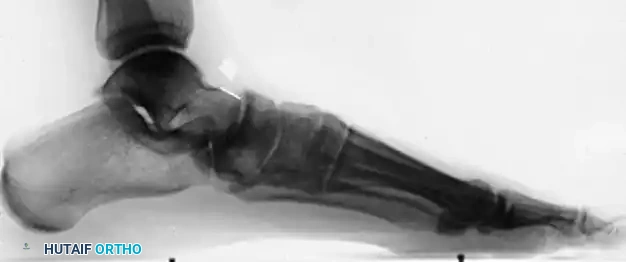

When the posterior tibial tendon (PTT) fails, the medial longitudinal arch collapses, leading to hindfoot valgus, midfoot abduction, and compensatory forefoot varus (supinatus). If the hindfoot is corrected to a neutral alignment, a fixed forefoot supinatus will cause the lateral border of the foot to bear excessive weight, leading to lateral column overload and recurrent deformity. Therefore, addressing the medial column is paramount.

The fundamental goal of the Cotton osteotomy is to restore the tripod effect of the foot—specifically, the weight-bearing distribution between the calcaneal tuberosity, the fifth metatarsal head, and the first metatarsal head.

By plantarflexing the medial column through the medial cuneiform, the surgeon effectively re-establishes the medial pillar of this triangle, ensuring a plantigrade foot following hindfoot correction.